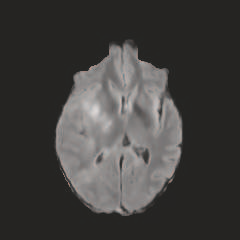

Multi-modal medical image completion has been extensively applied to alleviate the missing modality issue in a wealth of multi-modal diagnostic tasks. However, for most existing synthesis methods, their inferences of missing modalities can collapse into a deterministic mapping from the available ones, ignoring the uncertainties inherent in the cross-modal relationships. Here, we propose the Unified Multi-Modal Conditional Score-based Generative Model (UMM-CSGM) to take advantage of Score-based Generative Model (SGM) in modeling and stochastically sampling a target probability distribution, and further extend SGM to cross-modal conditional synthesis for various missing-modality configurations in a unified framework. Specifically, UMM-CSGM employs a novel multi-in multi-out Conditional Score Network (mm-CSN) to learn a comprehensive set of cross-modal conditional distributions via conditional diffusion and reverse generation in the complete modality space. In this way, the generation process can be accurately conditioned by all available information, and can fit all possible configurations of missing modalities in a single network. Experiments on BraTS19 dataset show that the UMM-CSGM can more reliably synthesize the heterogeneous enhancement and irregular area in tumor-induced lesions for any missing modalities.